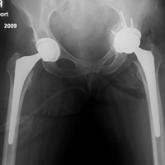

Management and Prevention of Intraoperative Acetabular Fracture in Primary Total Hip Arthroplasty

Intraoperative acetabular fracture (IAF) is a rare complication of primary total hip...